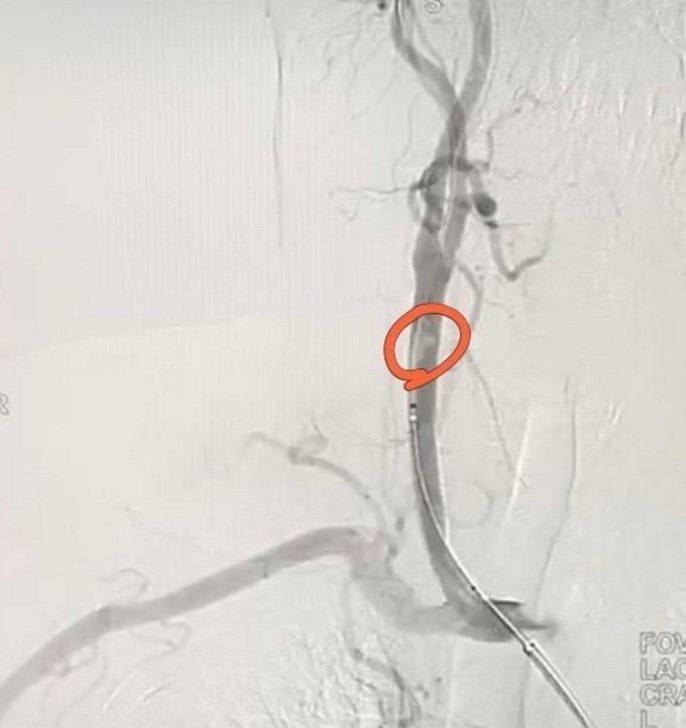

西安市一院神外血管组介入病例系列9轻症脑血管闭塞

脑血管造影提示左侧颈内动脉仅剩一残端显影